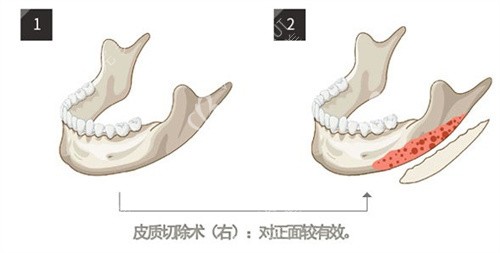

术前沟通时,刘医生没有急于推销方案,而是让我躺进CT扫描仪。半小时后,他指着屏幕上旋转的3D头骨模型说:"你的下颌角转折点偏低,但骨质厚度适中,适合做长曲线截骨。"更神奇的是,他拿出根据我颌骨数据打印的透明导板,严丝合缝地贴在我的下颌模型上,连神经血管走向都清晰标注。这种精密度让我悬着的心落了地——传统手术靠医生经验估算,而3D打印技术让每一毫米的截骨量都经过科学计算。

手术当天,麻醉后我沉沉睡去。醒来时,脸上缠着加压绷带,喉咙因插管有些干痛,但腹部那种翻江倒海的呕吐感并未出现。护士说刘医生采用了内窥镜辅助的小创口技术,切口仅藏在口腔内,外部不留疤。让我安心的是,他使用微动力系统的小磨头,像雕刻家般精细打磨骨面,避免伤及咬肌和面动脉。术后头一晚,镇痛泵帮我平稳度过,那种想象中"骨头被锯"的剧痛并未降临。